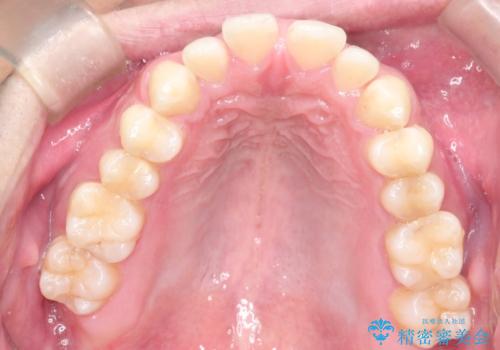

前歯の隙間を閉じたい 口元も下げたい ハーフリンガルによる抜歯矯正

上顎正中離開と、口唇の突出感がありました。

上下左右の歯を1本ずつ抜歯しして、上顎の前歯を後方に移動させるのと、正中の隙間を閉じる計画としました。

抜歯をせず上顎の正中離開のみの矯正もできましたが、患者様と相談して口元の改善も同時に行うために抜歯矯正の計画としました。